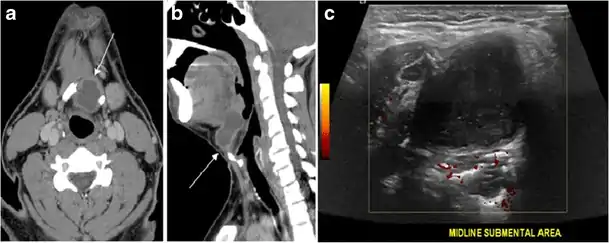

Fig. 16. Midline ectopic thyroid with Hashimoto's thyroiditis in a 49-year-old female patient. a Transverse greyscale ultrasound shows a 1.6 × 0.8 cm solid, well-defined, heterogeneous area (white arrow) in the midline, superior to the thyroid gland. It is iso-echogenic to the thyroid gland with no definite connection to the thyroid gland. b Transverse colour Doppler ultrasound shows significant increase in vascularity. c Axial enhanced neck CT scan at the level of thyroid cartilage demonstrates midline infrahyoid hyperdense soft tissue mass (white arrow) embedded within the strap muscle.[1]